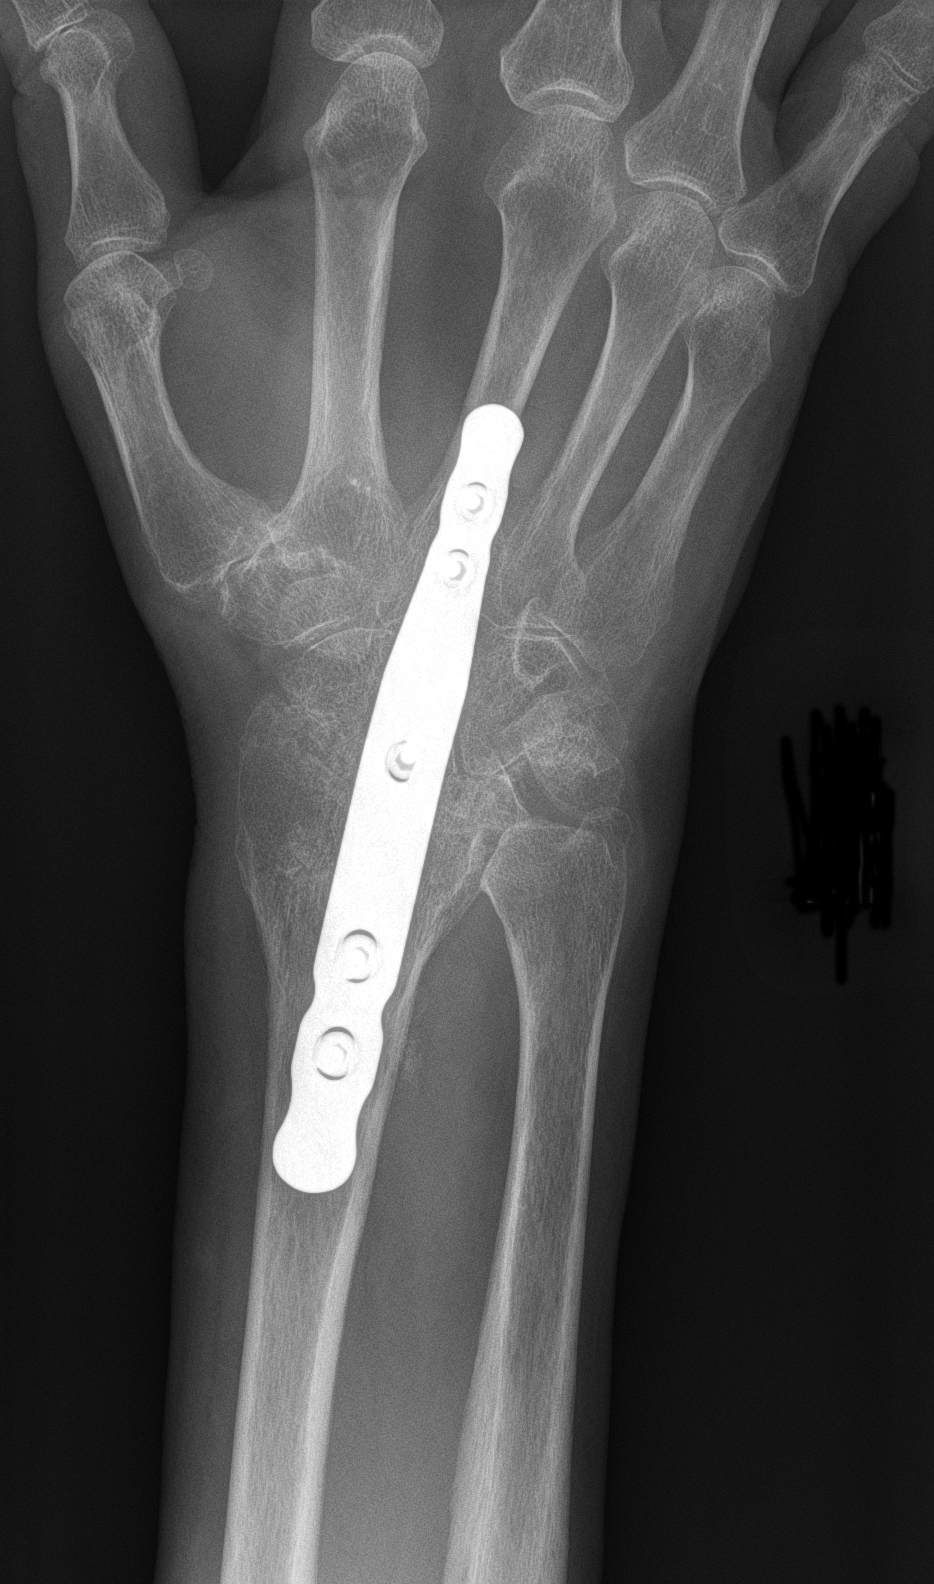

Wrist fusion

In a fusion, or arthrodesis, the bones of the wrist are held together with a plate, screws, and/or pins.